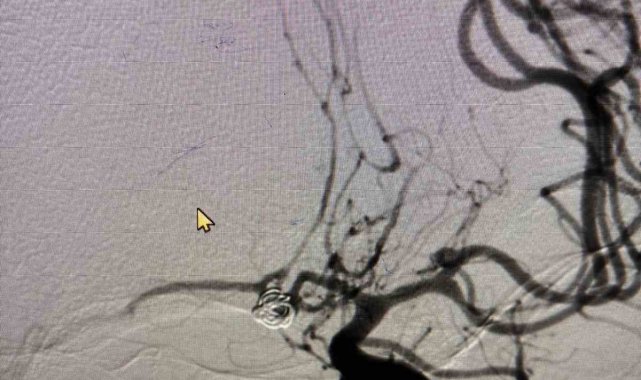

Aytaç, "Beyin baloncukları kanaması durumunda bu hastaların yüzde 10'luk kısmı kanama olur olmaz hayatlarını kaybeder. Geriye kalan yüzde 50'lik kısmı da bir ay içerisinde hayatlarını kaybeder. Çok ölümcül seyreden bir hastalıktır. Kanayan veya kanamayan beyin baloncuğu tespit edildiğinde o baloncuğun kapatılması ya da cerrahi işlem ile klipsleme denilen işlem ile baloncuğun ortadan kaldırılması gerekir. Diğer bir tedavinin ise kasıktan girilerek baloncuğun tespit edilerek metal örgüler ile baloncuğun kapatılması işlemidir. Bu yöntem, hastalarda hayat kurtarıcı bir işlemdir. Yeni başlayan baş ağrısı, bilinç bulanıklığı ve ateş gibi belirtileri olan hastaların, hiç vakit kaybetmeden acil servislere başvurmaları gerekmektedir" şeklinde konuştu.